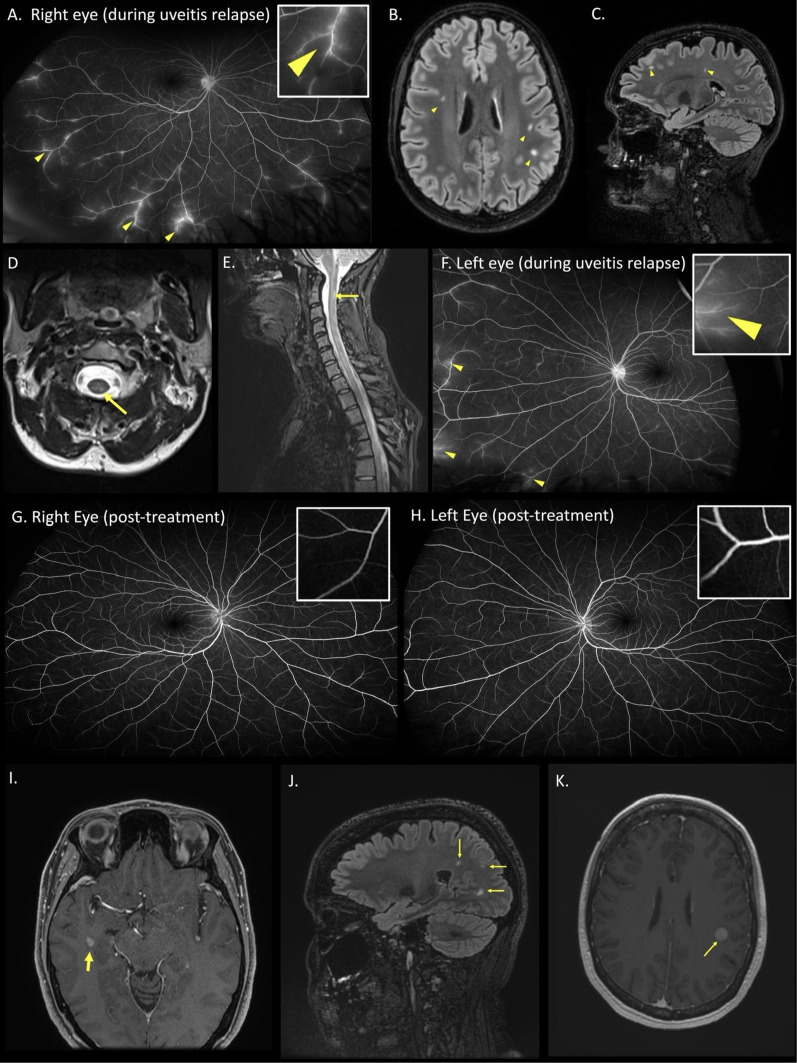

Intermediate uveitis (IU) may be associated with multiple sclerosis (MS), with both conditions possibly sharing pathogenic mechanisms. Two patients presented with bilateral IU. Despite targeted uveitis treatment with corticosteroids and methotrexate, both had ongoing disease activity with symptoms, and fluorescein angiographic abnormalities. Both were subsequently identified to have radiologically isolated MS in the absence of clinical demyelination. Treatment with natalizumab in isolation, led to rapid and sustained resolution of uveitis, enabling discontinuation of other immunosuppression. This case series adds evidence supporting use of alpha-4 integrins in the treatment of MS-associated uveitis, in addition to its known high-efficacy in MS.